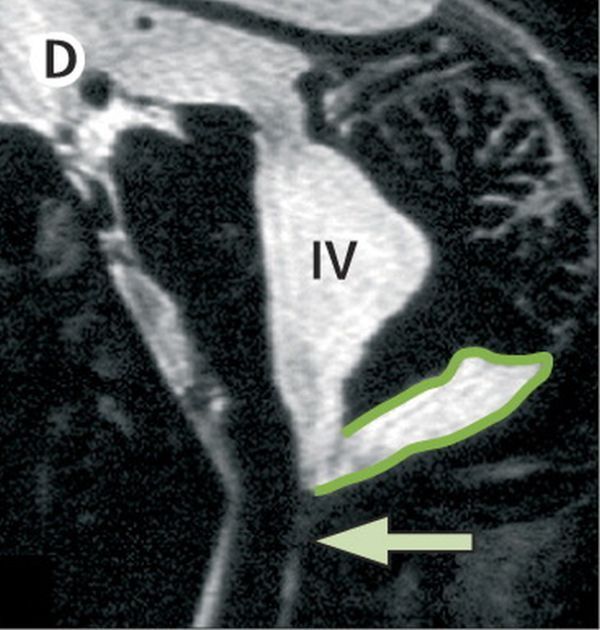

Снимок D: Т2-режим МРТ область задней черепной ямки.

Здесь ничего не стал дорисовывать. Зеленым указана киста (она может быть, как и причиной возникновения водянки головного мозга, так и ее следствием за счет атрофии головного мозга). Стрелкой указан уровень блока, отверстие Мажанди (один из основных сбросов ликвора).